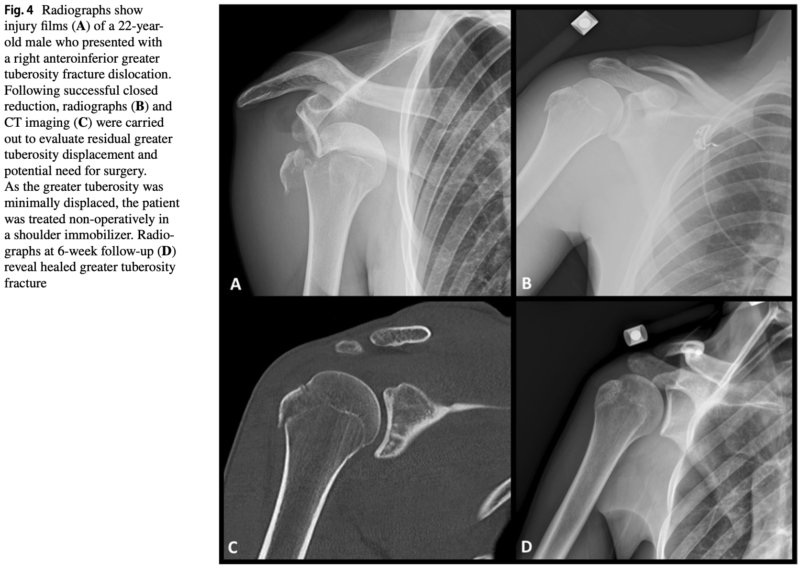

15時に来院された患者さんは, 上腕骨大結節骨折を伴う肩関節脱臼骨折.

その場で整復操作を試みましたが, 脱臼から3日が経過しており, 整復は困難.

入院していただき, 明日, 全身麻酔下で整復手術を行う方針としました.